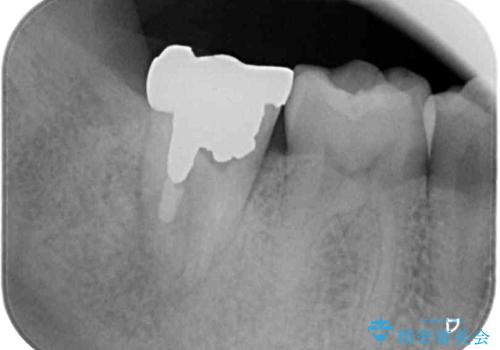

- 奥歯の虫歯治療を希望したものの、歯の高さが足りなくて治療ができないと言われ、来院された患者様です。

レントゲン撮影より、根尖部に病変が認められたため、根管治療を行った後に、歯冠長延長術を行うこととしました。